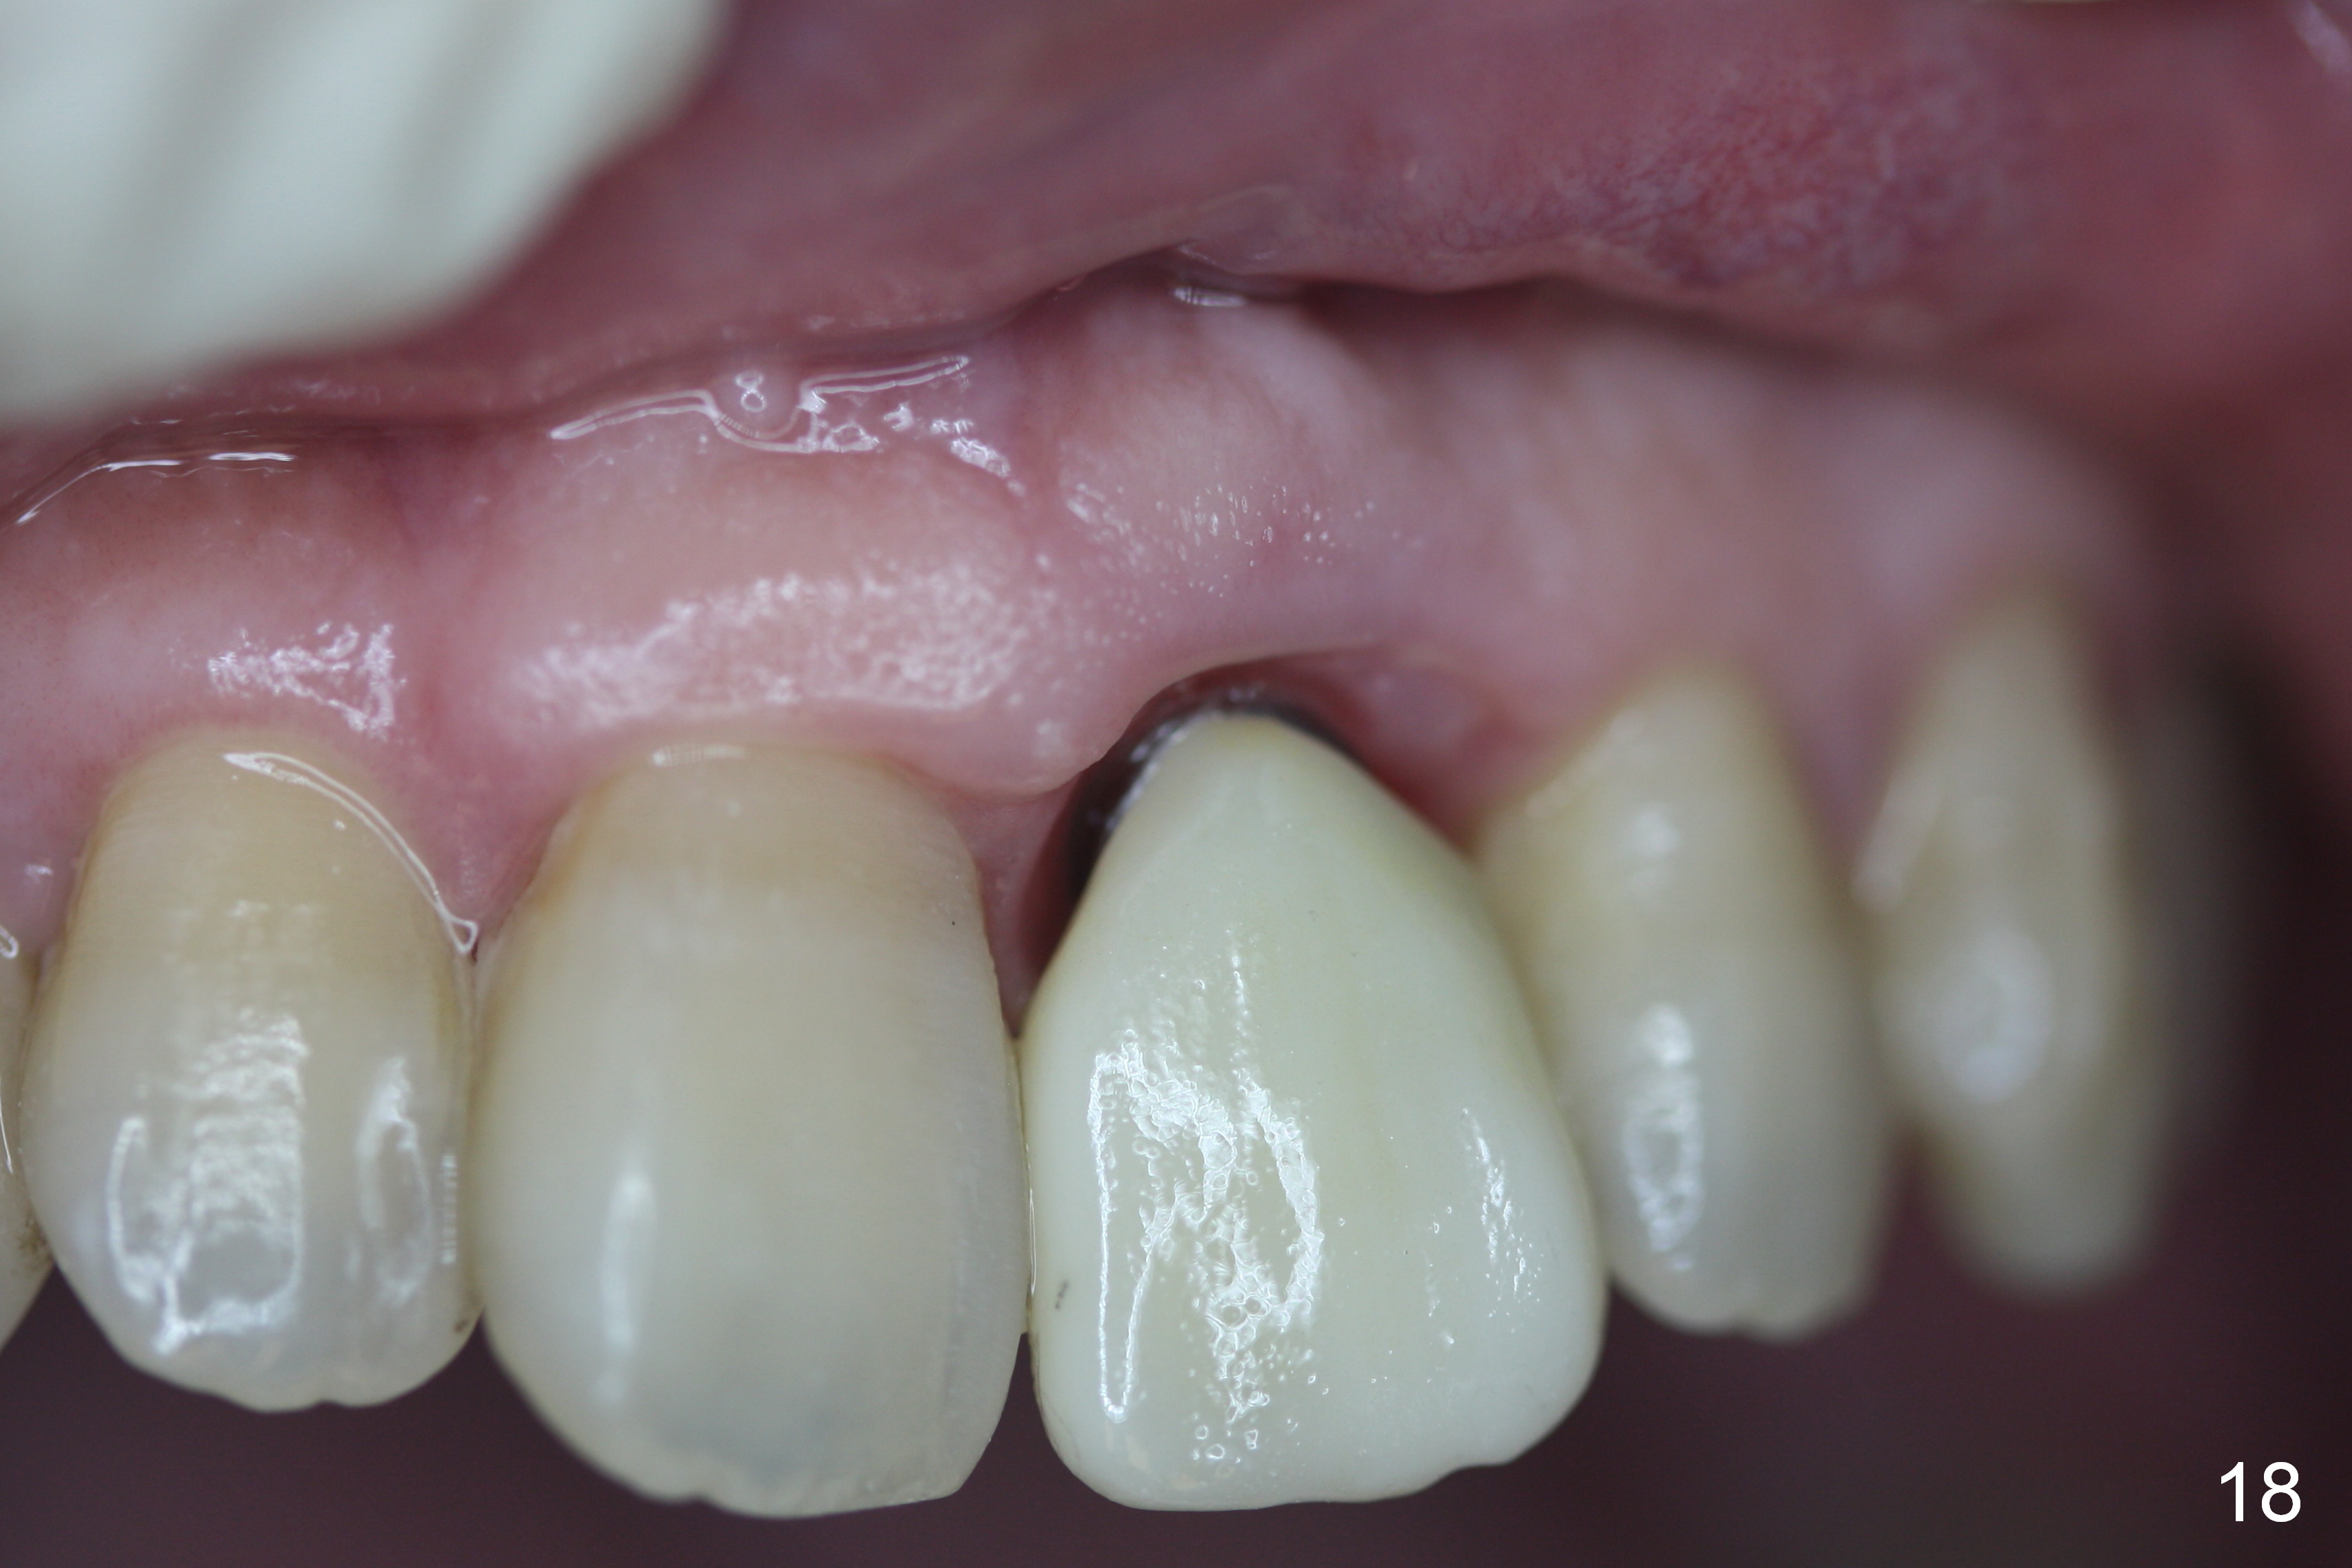

The permanent crown is temporarily cemented because of misshade and undercountour at the cervix (Fig.18).